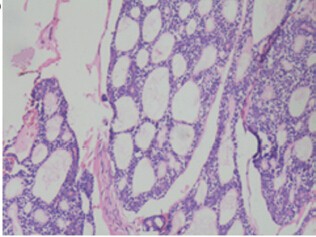

活检结果显示,肿瘤细胞呈筛状生长模式,由基底样细胞深染棱角核包围假性囊肿,使整个结构呈现出典型的“瑞士奶酪”样